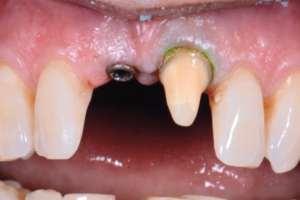

Si presenta al nostro studio una signora di mezza età con anamnesi di pregresso trauma agli incisivi centrali superiori 11 e 21. La paziente presenta un severo riassorbimento pulpare interno con perdita della parete palatale dell’11 e una comunicazione completa endodonto-parodontale (Figg. 1-4). Si decide di rimuovere l’11 sostituendolo con un impianto post-estrattivo. Per ottimizzare l’estetica dei due incisivi, disallineati e parzialmente sovrapposti, si decide di preparare anche il dente 21, già devitalizzato.

- Figg. 1-3 – Situazione clinica iniziale

- Fig. 2

- Fig. 3